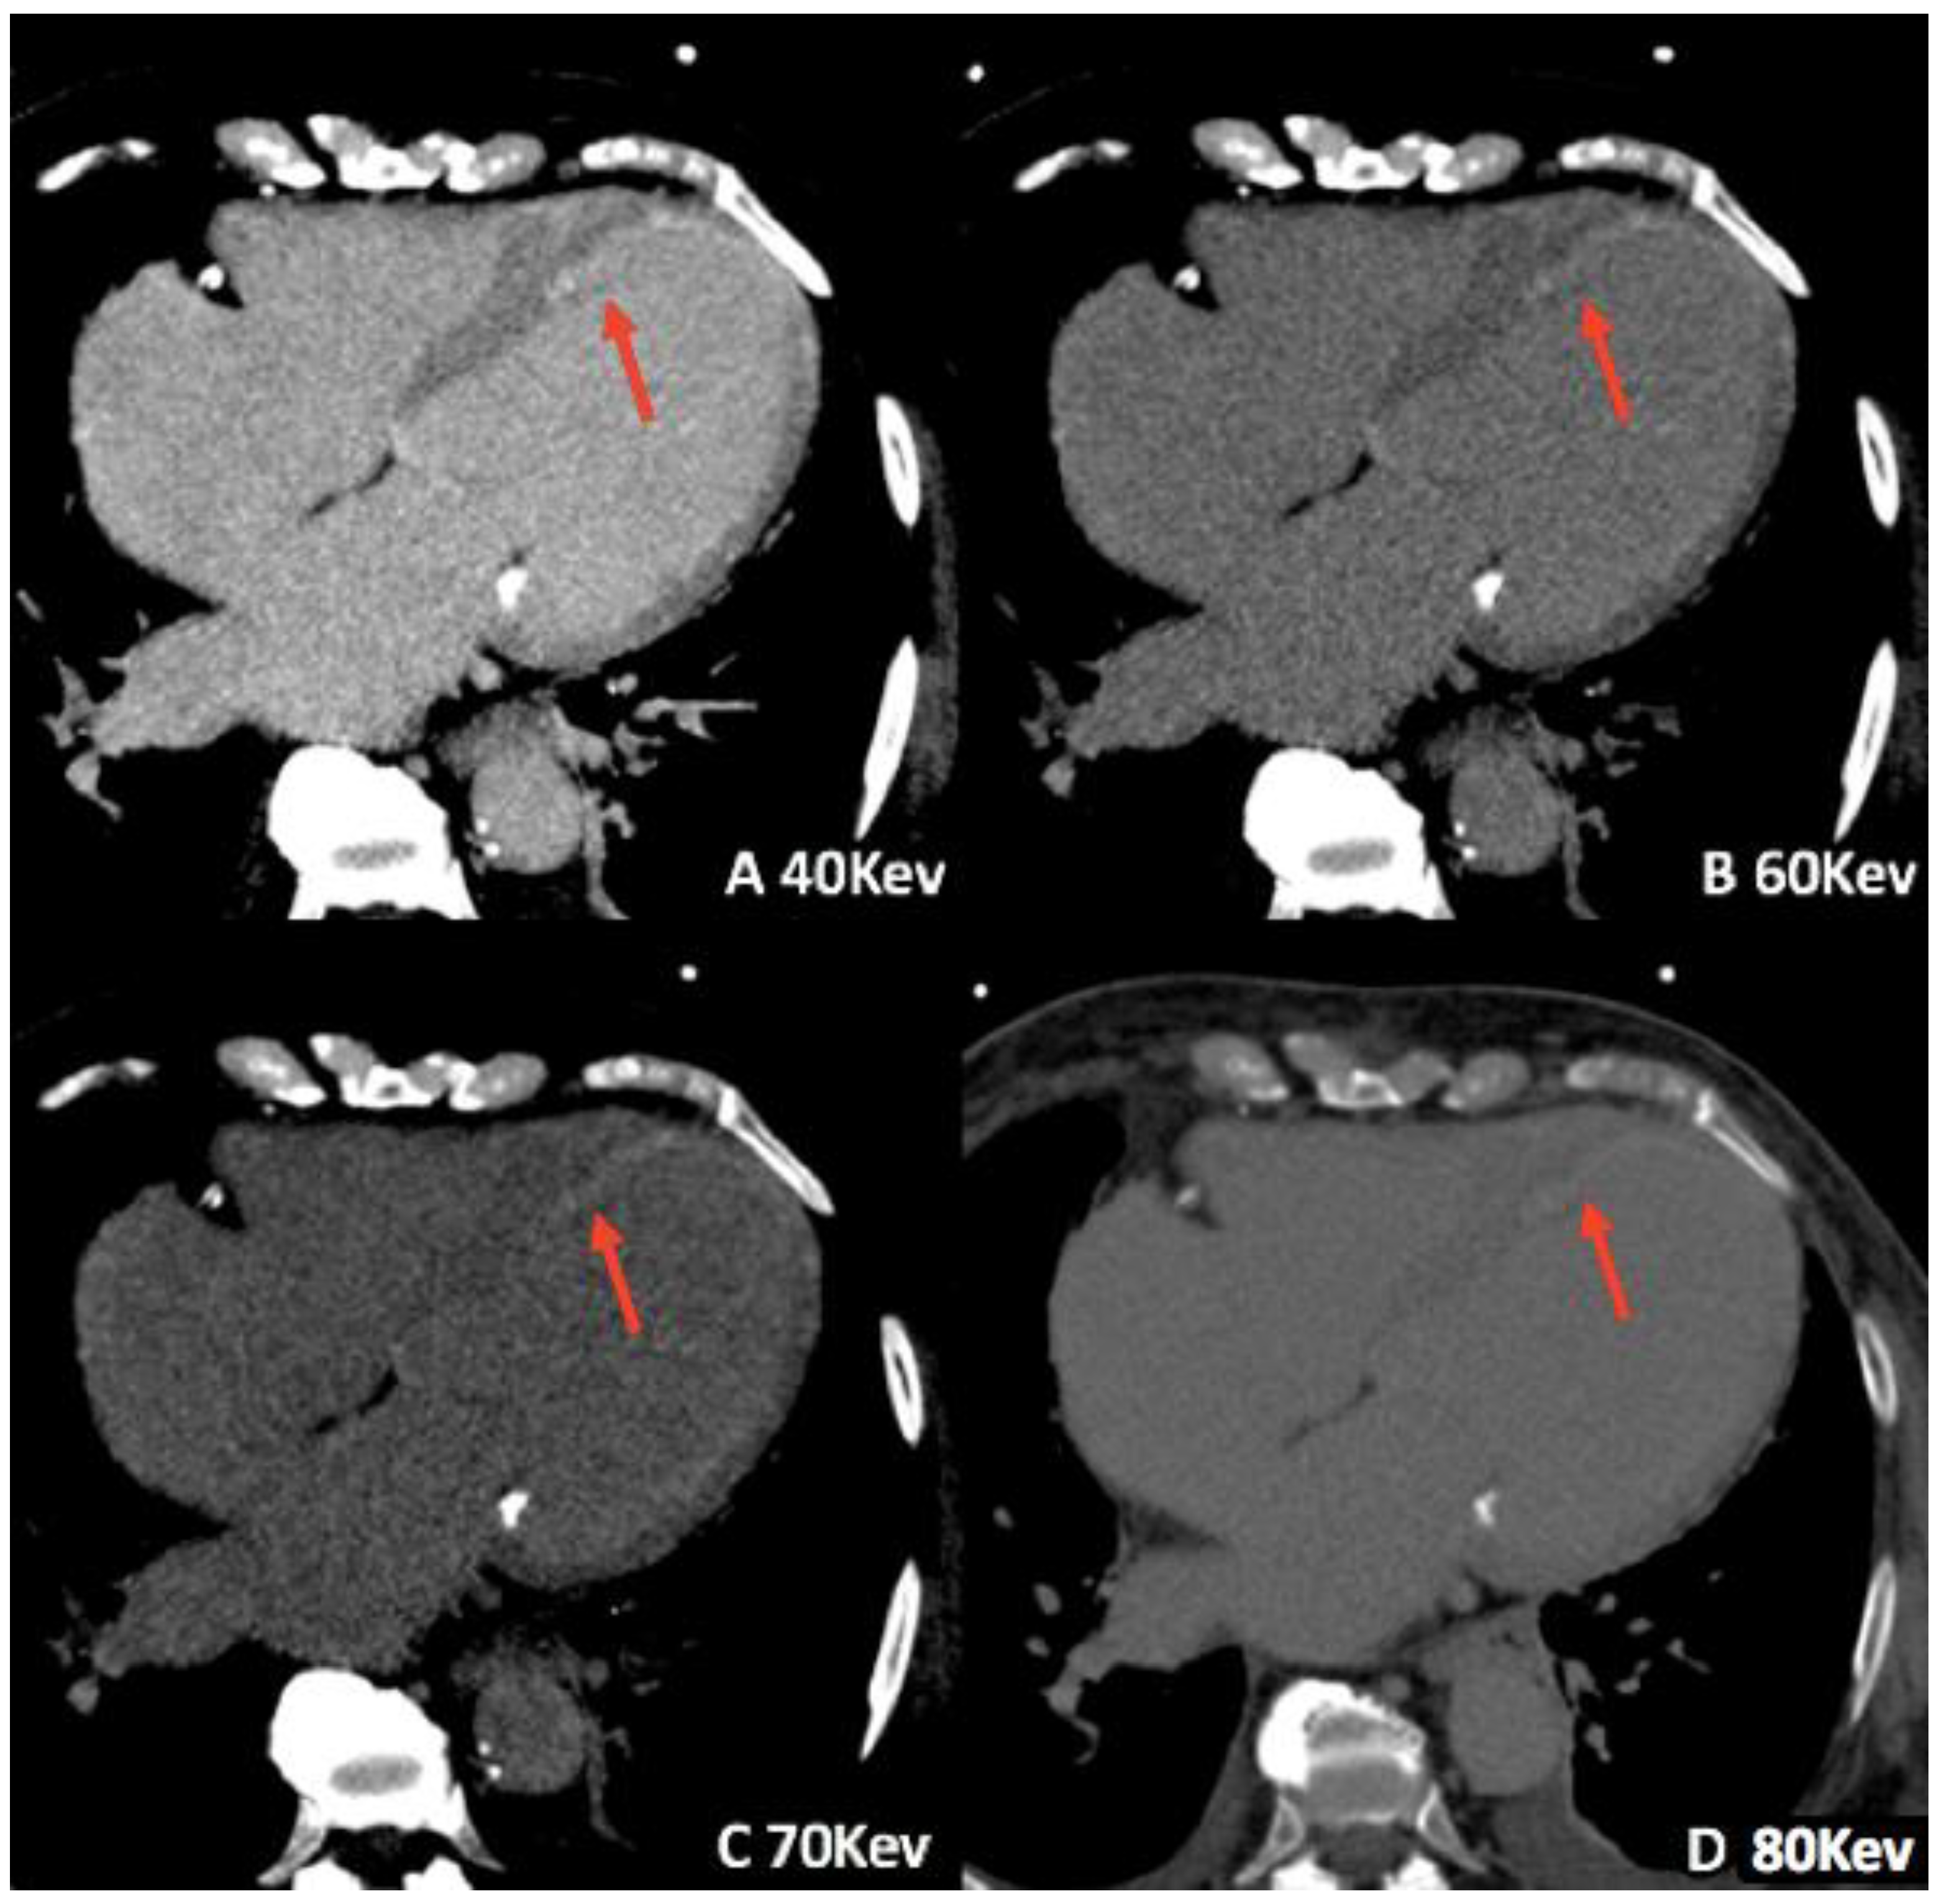

3.1. Virtual Monoenergetic Imaging (VMI)

- Zeng, Y.; Geng, D.; Zhang, J. Noise-optimized virtual monoenergetic imaging technology of the third-generation dual-source computed tomography and its clinical applications. Quant. Imaging Med. Surg. 2021, 11, 4627–4643. [Google Scholar] [CrossRef]

- Beeres, M.; Trommer, J.; Frellesen, C.; Nour-Eldin, N.-E.A.; Scholtz, J.E.; Herrmann, E.; Vogl, T.J.; Wichmann, J.L. Evaluation of different keV-settings in dual-energy CT angiography of the aorta using advanced image-based virtual monoenergetic imaging. Int. J. Cardiovasc. Imaging 2016, 32, 137–144. [Google Scholar] [CrossRef] [PubMed]

- Albrecht, M.H.; Scholtz, J.-E.; Hüsers, K.; Beeres, M.; Bucher, A.M.; Kaup, M.; Martin, S.S.; Fischer, S.; Bodelle, B.; Bauer, R.W.; et al. Advanced image-based virtual monoenergetic dual-energy CT angiography of the abdomen: Optimization of kiloelectron volt settings to improve image contrast. Eur. Radiol. 2016, 26, 1863–1870. [Google Scholar] [CrossRef]